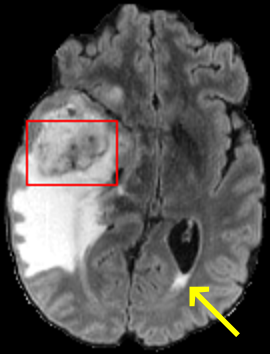

To test the impact of the iterative refinement on YODA’s translation quality, we compared regression and diffusion sampling on the RS data and present additional generation examples in Fig. 6. We observe that diffusion sampling visually resembles the appearance of the acquired images. Regression sampling preserves key anatomical features – the GM/WM boundary, WMHs (Fig. 4), the outline of the pallidum (Fig. 6) – but omits many high-frequency features. To investigate whether iterative refinement during diffusion sampling adds relevant and systematic medical information or only imitates acquisition noise, we performed ExpA sampling, i.e. averaging the output of several ( or ) diffusion trajectories. We observed a gradual loss of high-frequency details when increasing the (see also the supplementary video), indicating that the effect of the iterative refinement is non-systematic. For , the images are visually almost indistinguishable from the initial regression solution (see the supplementary video, and Fig.4 and 6). We directly compared the synthesis results of ExpA () and regression sampling quantitatively and found the differences to be minimal (SSIM: 99.73%, PSNR: 45.30 dB), i.e. diffusion sampling approaches the initial regression solution for a high . The quantitative analysis of the image quality (Tab. 1) showed that diffusion sampling impairs the assessed SSIM and PSNR in comparison to regression sampling for both the in- and external test sets, which we attribute to noise generation (Sec. 3.1). In turn, ExpA averages improved both metrics and, for , performed mostly on par with the regression solution in both test sets in terms of SSIM, while the PSNR in the RS was slightly increased (Tab. 1). However, we observed that ExpA sampling YODA improves the replication of systematic 3D low-frequency image intensity drifts (bias fields) due to the 3D synchronization in 2.5D diffusion sampling. Yet, this apparent advantage did not generalize to the external MBB dataset, as bias fields are MR protocol-specific.

When analyzing the RS synthesis results (Fig. 4), we noted that most reference methods strive to imitate realistic images, but several artifacts can be observed such as hallucinated WMHs (SynDiff) and salt-and-pepper noise (SynDiff, I2I-Mamba, ResViT).